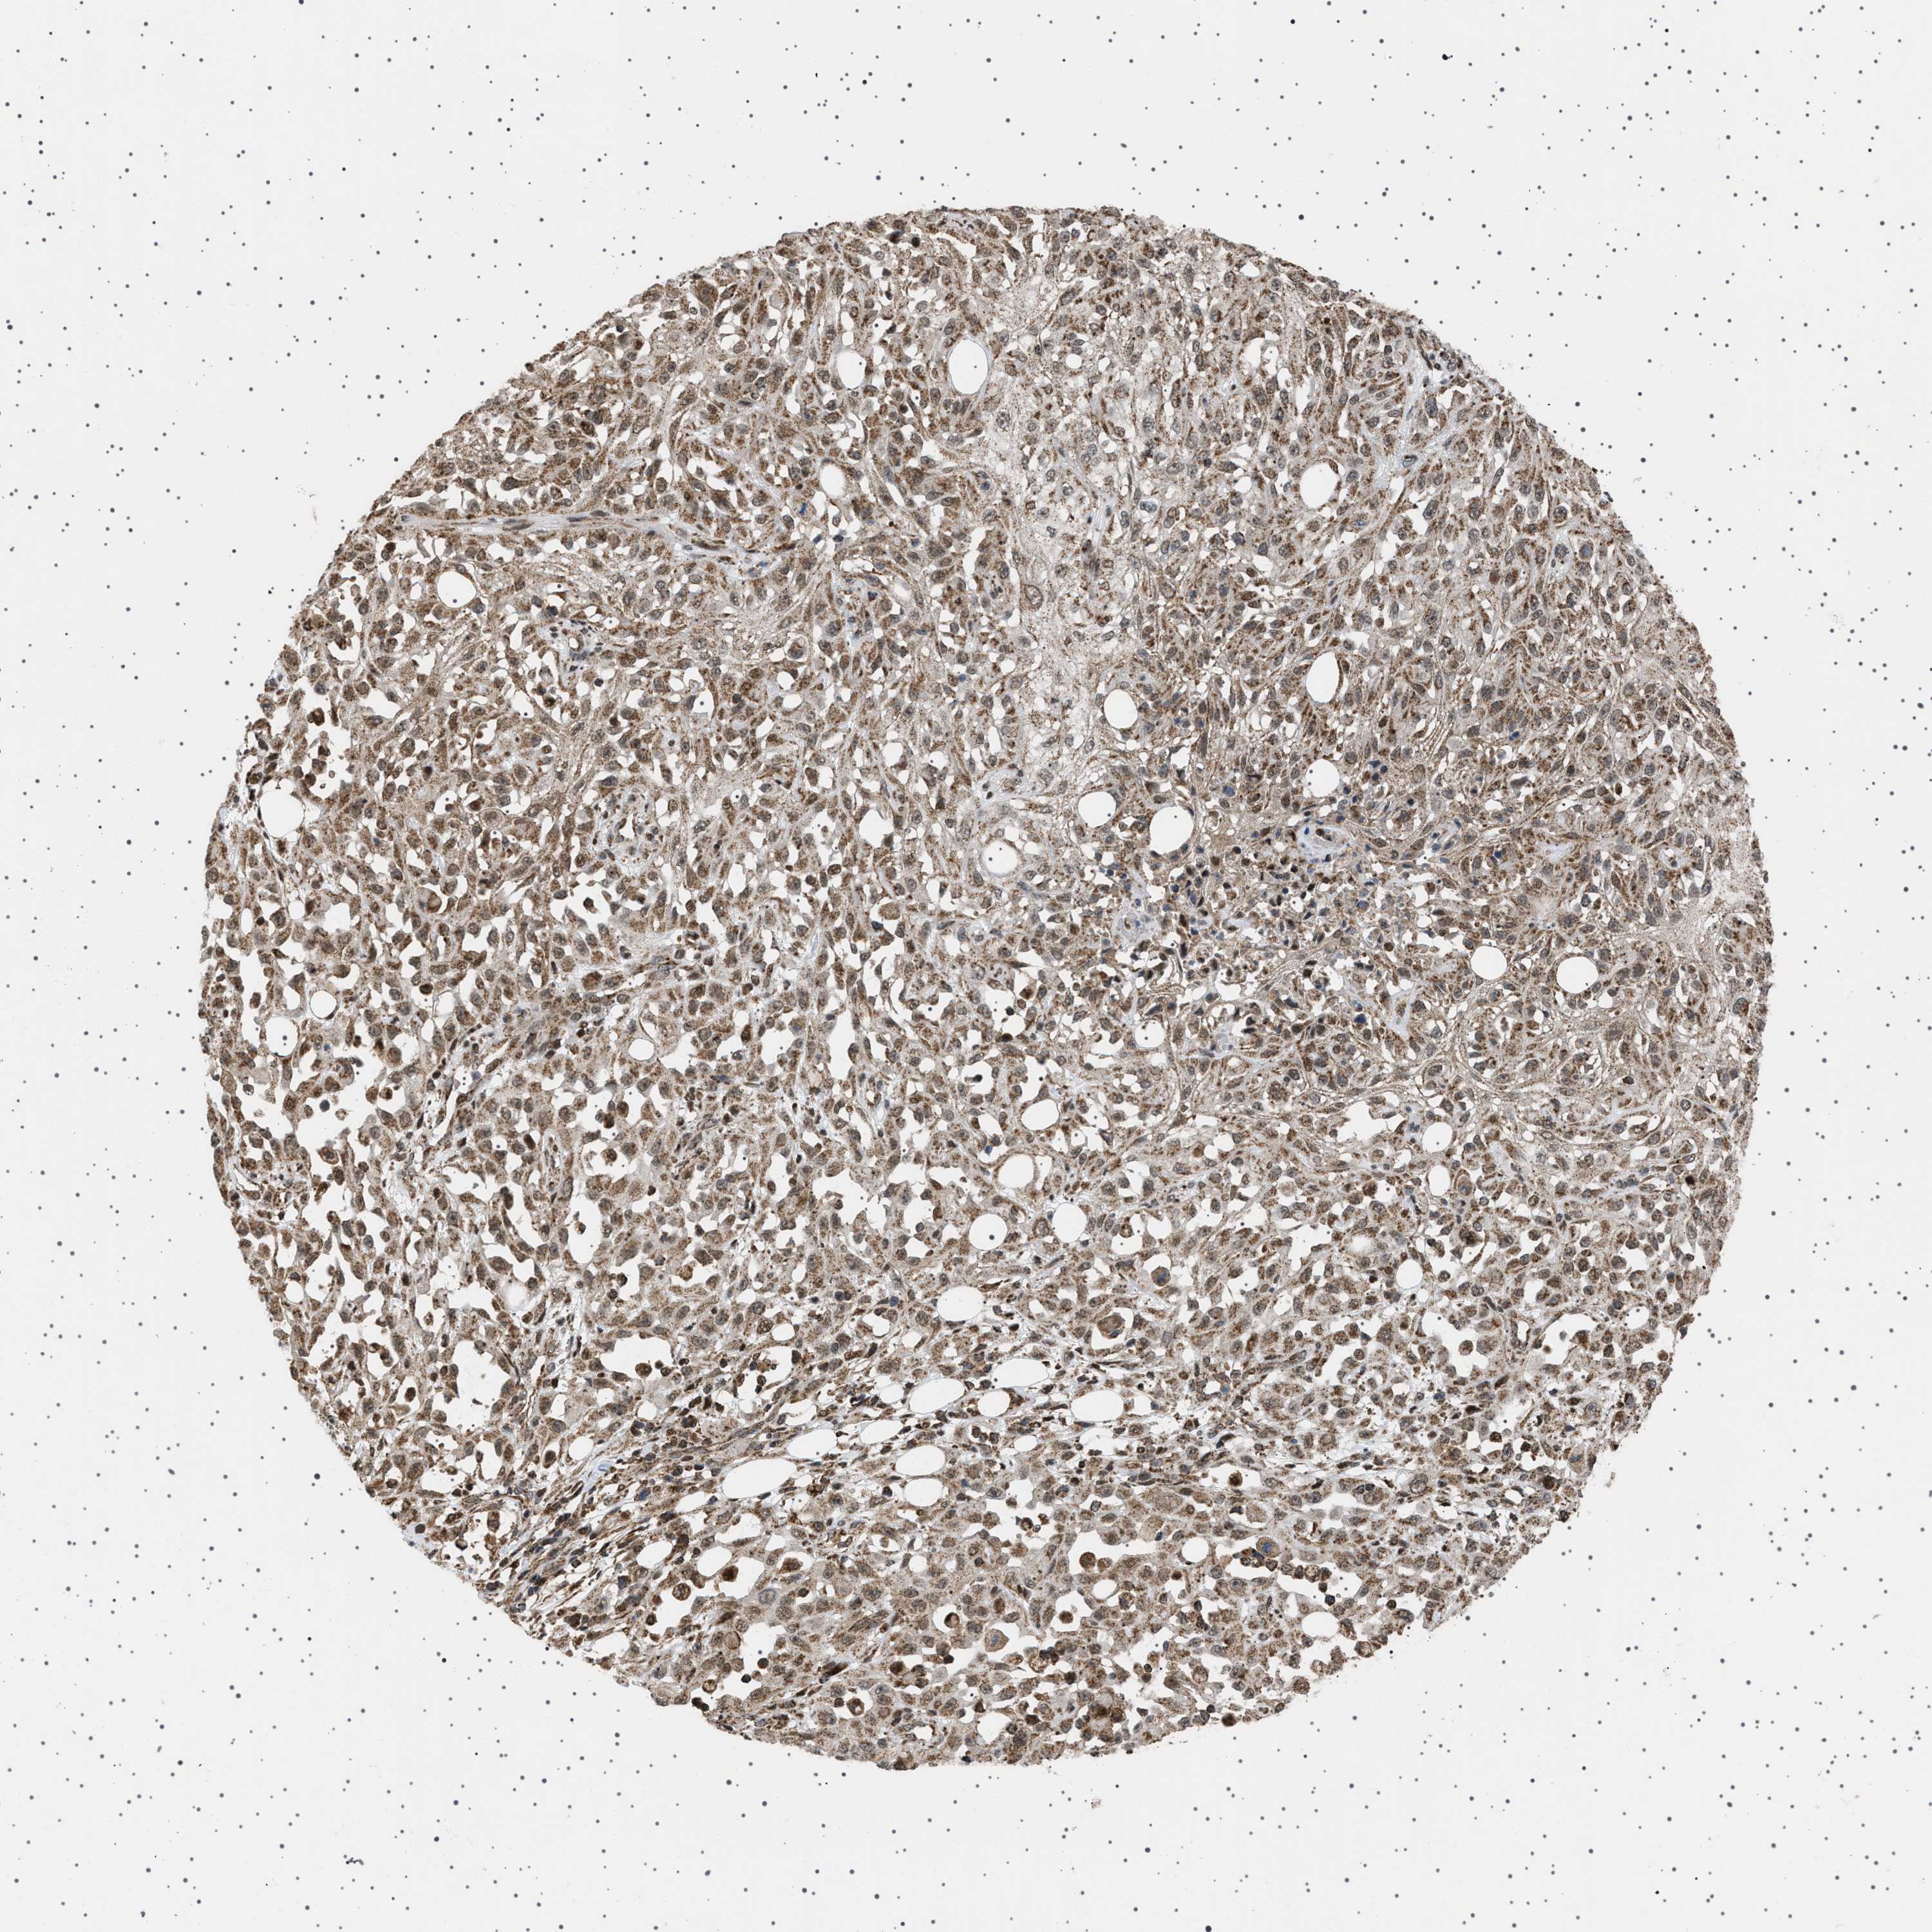

SKIN CANCER - Protein expressioni

A mouse-over function shows sample information and annotation data. Click on an image to view it in a full screen mode. Samples can be filtered based on level of antibody staining by selecting one or several of the following categories: high, medium, low and not detected. The assay and annotation is described here.

Antibody stainingi

Antibody staining in the annotated cell types in the current human tissue is reported as not detected, low, medium, or high, based on conventional immunohistochemistry profiling in selected tissues. This score is based on the combination of the staining intensity and fraction of stained cells.

Each image is clickable and will lead to virtual microscopy that enables deeper exploration of all samples and also displays staining intensity scores, fraction scores and subcellular localization as well as patient and tissue information for each sample.

Antibody HPA017214

Staining

High

Medium

Low

Not detected

Intensity

Strong

Moderate

Weak

Negative

Quantity

>75%

75%-25%

<25%

None

Location

Nuclear

Cytoplasmic/membranous

Cytoplasmic/membranous,nuclear

Basal cell carcinoma